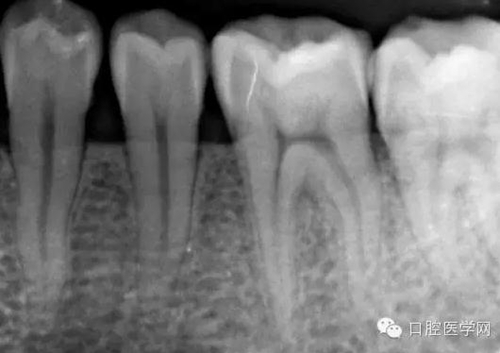

治療過程:26開髓,修整髓腔后探及頰側(cè)近遠(yuǎn)中雙根管,腭側(cè)一根管,10#k銼初探腭根較為通暢,頰根可以深入,較灣,較細(xì),初步測得根管長度約為19mm,SANI S3根管口處理銼SU敞開根管中上段,建立直線通路后測量工作長度,近中頰根19mm,遠(yuǎn)中頰根18.5mm,腭根19mm,設(shè)置馬達(dá)轉(zhuǎn)速:500RPM,n扭力:2.5N.CM,04/20、06/25、04/35,3S銼完成根管預(yù)備,三根管預(yù)備后觀察髓腔狀況,發(fā)現(xiàn)近中頰根根管口偏舌側(cè)有一線行裂紋,(恍然大悟)患牙疼痛的根源在此,牙隱裂引發(fā)急性牙髓炎。降合,沖洗根管,紙尖干燥根管后,導(dǎo)入氫氧化鈣,氧化鋅暫封。此時(shí)牙齦出血已停止,交代醫(yī)囑,不適隨診。